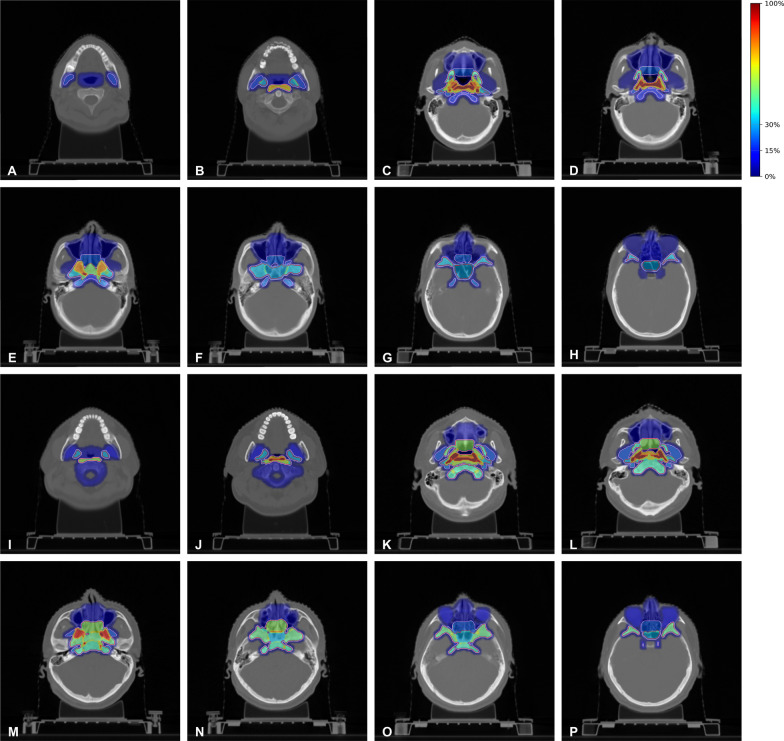

However, in early-stage disease (T1–T2), these structures may not be routinely included in the delineation of the CTV, given the low risk of local recurrence: posterior ethmoid sinus (9.1%), inferior orbital fissure (9.1%), lateral pterygoid muscle (3.0%), hypoglossal canal (3.0%), and cavernous sinus (3.0%). Based on the differences in local recurrence risk, our team generated high-risk maps of local recurrence for early-stage and locally advanced cases using a python script (Fig. 1).

Fig. 1.

Recommended clinical target volume according to the percentage of local recurrence in cases of early and locally advanced stage of nasopharyngeal carcinoma. A–H Demonstrated the risk of local recurrence of each anatomic structure and recommended delineation of clinical target volume (CTV) in T1–T2 case with nasopharyngeal carcinoma, at the level of cranial border of C2, midpoint of C1, hard palate, midpoint of maxillary sinus, foramen lacerum, great wing of sphenoid bone, inferior orbital fissure and midpoint of orbit. I–P Demonstrated the risk of local recurrence of each anatomic structure and recommended delineation of clinical target volume (CTV) in T3–T4 case with nasopharyngeal carcinoma, at the level of cranial border of C2, midpoint of C1, hard palate, midpoint of maxillary sinus, foramen lacerum, great wing of sphenoid bone, inferior orbital fissure and midpoint of orbit. The color bar showed the risk of local recurrence. The pink and red line showed the iso-risk line of 15% and 30% of local recurrence. In our study, the iso-risk line of 15% was selected as the recommended contouring of CTV. It was noteworthy that lateral pterygoid muscle, posterior ethmoid sinus, inferior orbital fissure and cavernous sinus were not included in the delineation of CTV in early-stage disease, but were encompassed by CTV in locally advanced disease